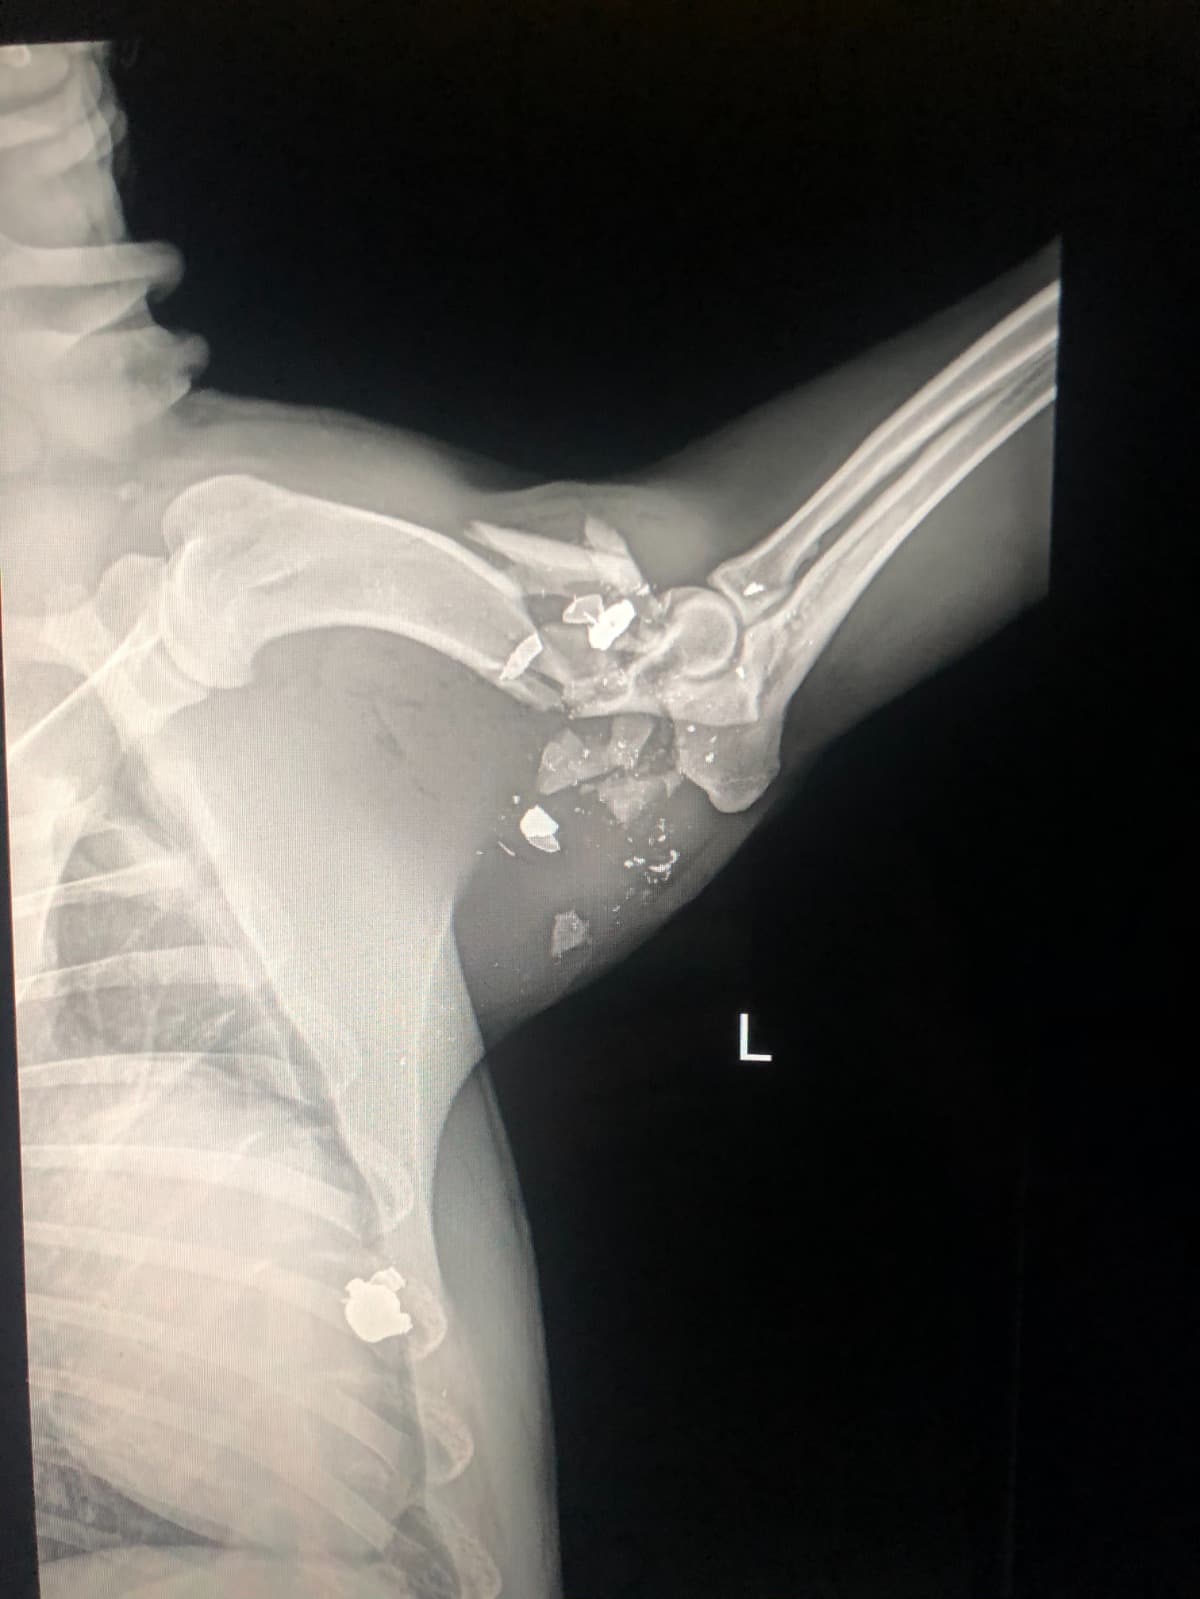

On August 13, 2021 at approxamitaley 10 a.m. I was woken up to all of my dogs going crazy which is something that is very unusual and out of the ordinary. I jumped up out of bed to see what all the commosion was and the first thing i see when i open my back door was my baby boy euro leaning against my patio door lifting his leg bleeding out . I was stunned with confusion as to how this happened and what was going on! i looked to my left and seen my neighbors heading back in their home, after i paid my attenton to my poor euro who was badley wounded I immediately picked him up to get him cleaned up and it looked like he had took a blood bath. i went back in my home partially ripped my curtains off my window and placed them on the floor along with him on top. With me panicking cleaning him up trying to figure out how this happened i went outside to look for answers. i calmly walked over to my next door neighbors house knocked on their door only for them to be hiding behind there front door. As i walking over back to my house upset , i was stopped by my front neighbors roofer worker, my front neighbor was getting his roof worked on By a roofing company when all of this happened. keep in mind i was asleep when all this happened as well. I had a group of 10+ workers come to me saying they witnessed my neighbor calmly walk to the sideline of the fence that seperates mine and his yard and fired his weapon at my poor dog who was under the tree minding his buisness. When i heard that i was raging with anger and walked back over and said some foul language i mean who wouldnt right? I started thinking about my reaction and behavior and stopped ran back home to get my boy some help. Me and my brother then loaded him up onto the truck and immediatley rushed to the closest Aniaml ER. Only then to hear the news that his bones were in pieces and our only options was to umputate it or put him down. not only that we were handed a enourmes Vet bill for the procedure and for the time and labor it was like a hammer hitting you back to back. As we waited outside the Animal ER trying to figure out what to do A Kind Police officer passed us and Seen the sorrow in our faces and may have seen all the blood we were covered in as well and asked about our situation. He wanted to take matter in his hands as fast as he could, so we rushed together back to the scene and got all the information he needed. We are in a desperate time of need and i hate to do stuff like this but anything at this moment helps . as of august 14 at approximietly 8:19 a.m. we were notifed By Dr.Marcus that our boy euro made it through surgery and has a long road to recovery ahead of him. This is just the beginning of his new life. He now has alot to adjust to because of the descision's and foul action my neighbor decided to do. thank you for the time you guys took to hear my story i wouldnt wish this upon anyone else. Again thank you for you time and concerns.